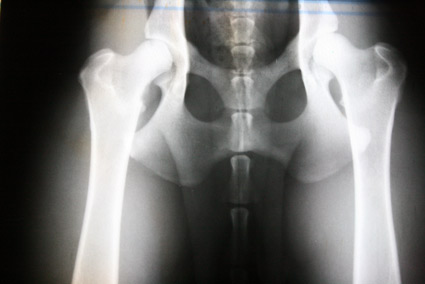

Hier nun einige HD Röntgenbilder:

| HD:E/HD-schwer/HD 4-5 |

E/1 |

= Grad3 (schwer) |

HD-4 |

schwer |

Das gesamte Gelenk ist stark verändert, evtl. eine vollständige Luxierung, NORBERG-Winkel unter 90 Grad |

E/2 |

= Grad4 (sehr schwer) |

HD-5 |

sehr schwer |